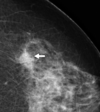

Ix: halo shape on mammography and diagnosed by US

How can you tell whether a breast cyst is malignant or not by US?

Aspirate either free hand or US guided.

Can exclude cancer if lump disappears on US after aspiration or if fluid free of blood. If not then send cystic fluid for cytology

Ix: Positive traumatic history and/or hyperechoic mass on US. Look like malignancy on mammogram if fibrotic lesion so core biopsy